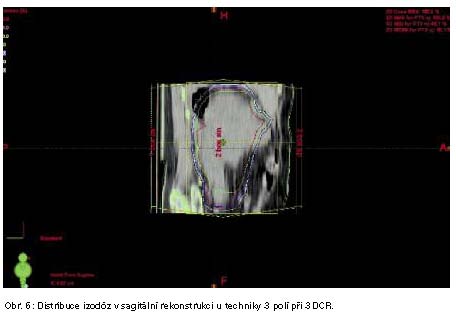

Léčba SMP zářením byla u 4 pacientů (obr. 4., 5., 6.) zářením, imunoterapii 1x a chemoterapií 1x.